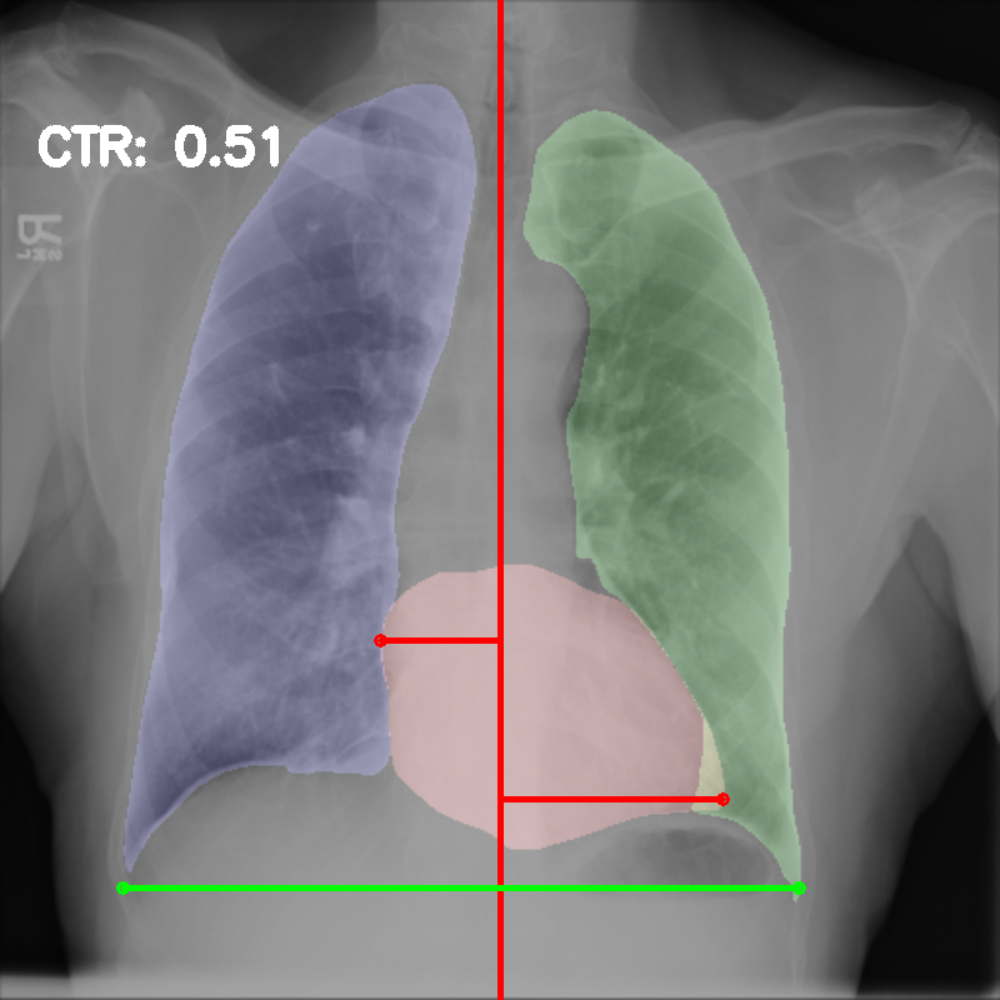

Chest radiography is the most common tool for detecting cardiomegaly due to the low cost and high availability of devices to obtain chest X-ray images. From chest X-ray images, radiologists employ CTR as one of the most important indicators of cardiomegaly due to the simplicity of the calculation. CTR of a chest X-ray image is calculated as cardiac diameter (the diameter of the heart) divided by the thoracic diameter (the diameter of the chest). Specifically, CTR can be calculated from three measurements, , the midline-to-right heart diameter, , the midline-to-left heart diameter, and , the internal diameter of chest [2, 3], as

| (1) |

where and is measured from the greatest perpendicular diameter from midline to right and left heart border, respectively. Figure 1 visualizes the details of CTR calculation. A CTR value of is generally considered to indicate the upper limit of normal.

3.5 Cardiothoracic Ratio Calculation

After obtaining the masks, we calculate CTR with equation 1. We calculate cardiac diameter, , by finding the extreme points on the x-axis of the heart mask and calculate their x-axis distance. Thoracic diameter, , is calculated from extreme points from the lung mask. Figure 4 demonstrates the calculation of each component.

After obtaining heart and lung segments, we calculated , , and and marked them on the image along with CTR value calculated from Equation 1.

Figure 6 shows examples of our CTR calculation, where CTR values along with their , and measurement points are correctly identified. In this image, cardiomegaly is correctly detected by CTR value of .

Figure 7 shows cases where our CTR calculation algorithm is incorrect due to failure to obtain accurate heart mask.

However, upon manual inspection of the images, we found a relatively high number of mild cardiomegaly cases that are not included in the dataset labels. Figure 8 shows sample chest X-ray images containing no-cardiomegaly labels with detected CTR values on range. This reflects the general sentiment that dataset labels are noisy and may contain errors, making it harder to analyze our algorithm. It also illustrates the value of an algorithmic "second opinion" to catch potential errors from both human and NLP algorithms used to generate the labels.